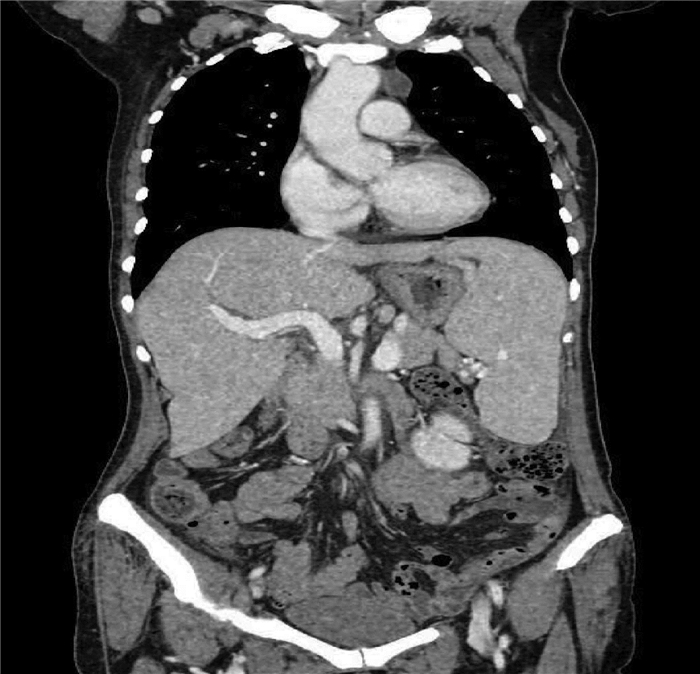

Construction of a new patient-derived xenograft model of human liver cancer in mice with normal immunity

Huixin TANG, Shanshan LI, Feng HONG, Yanzhen BI, Quanyi WANG, Xiaobei ZHANG, Shumin CHENG, Zhongping DUAN, Zhenfeng SHU, Yu CHEN

2021, 37(11): 2584-2588. DOI: 10.3969/j.issn.1001-5256.2021.11.019

Abstract(2475) HTML (633) PDF (3030KB)(178)

Abstract:

Objective  To establish a new patient-derived xenograft (PDX) model of human liver cancer by inoculating the complex of human primary liver cancer cells and a novel microcarrier (microcarrier 6) into mice with normal immune function.  Methods  Primary liver cancer cells were isolated and extracted from the fresh human liver cancer tissue of five patients and were then co-cultured with microcarrier 6 to construct a three-dimensional tumor cell culture model in vitro. According to the type of graft, 75 male C57BL/6 mice were divided into cell control group, microcarrier control group, and experimental group (each sample corresponded to three groups, with 15 groups in total and 5 mice in each group). The liver cancer cell-microcarrier complex was implanted into the mice by subcutaneous inoculation, and tumor formation time, tumor formation rate, and histopathological manifestations were observed. The Fisher's exact test was used for comparison of categorical data between two groups.  Results  As for the liver cancer cells from the five patients, tumor formation was observed in the mice corresponding to three patients. In these three experiments, tumor formation was not observed in the control groups and was only observed in the experimental groups, and 12 of the 15 mice in the experimental groups had successful tumor formation, with a tumor formation rate as high as 80%, which was significantly different from that in the cell control groups and the microcarrier control groups (all P < 0.05). The tumor formation time was 5-7 days; the xenograft tumor grew rapidly, and HE staining showed nested or flaky cells with obvious heteromorphism, with the presence of pathological mitosis; immunohistochemical staining showed positive CK8/18, Hep, and Gpc-3, which was in accordance with the characteristics of human liver cancer cells.  Conclusion  This experiment successfully establishes a new PDX model of human liver cancer based on the complex of microcarrier 6 and human primary liver cancer cells in mice with normal immunity. This model can be used to better elucidate the mechanism of the development and progression of liver cancer in the body with normal immunity, and besides, it also provides a new animal model with higher value for the precise treatment of liver cancer.